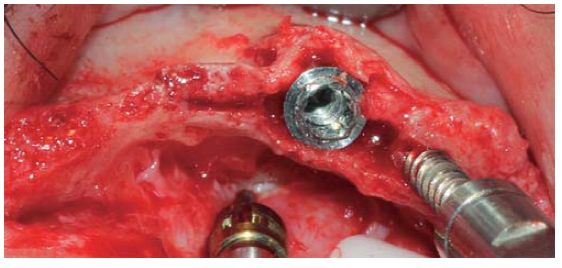

A full thickness incision over the crest was performed, raising a mucoperiosteal flap exposing bone table up to 4 mm from the top of the crest in vestibular direction; from that point the flap was divided into partial thickness (Figure 3). After this, impact points were marked in designated places according to surgical guide for implant placement; perforations were initiated with a 1.6 mm diameter burr in order to determine desired implant depth and axis. After this, a ridge was created on the crest with a diamond burr, fracturing cortical bone to create chisel's access to cancellous bone, and with the aforementioned, bone tables were separated until reaching a 5 mm depth (Figures 4 y 5). Perforations were further continued with a 2.0 diameter burr (Figure 6), and vestibular table expansion was undertaken creating greenstick fracture with the expanders, until reaching sufficient osseous bed diameter (3.2 mm diameter) (Figures 7 y 8). Implants were then placed at a 25 rpm speed and 35 Nem torque (Figures 9 y 10). After this, a particulate bovine bone graft was placed (Bonefill® Bionnovation Biomedical, Sao Paulo, Brazil) with the aim of preserving integrity of vestibular bone tables (Figure 11). All these procedures were repeated for placement of all six implants. Finally, sutures were undertaken with monofilament nylon 5/0.

Figure 4 Diamond disc (0.5 mm thick) used to create a crest groove passing through cortical bone and allowing access for bone chisel.

Figure 5 Bone chisel entering medullar portion, separating cortical ridge leading to greenstick fracture.

Figure 8 Bone expander placed distally with respect to the preparation, avoiding a fracture of the vestibular table.